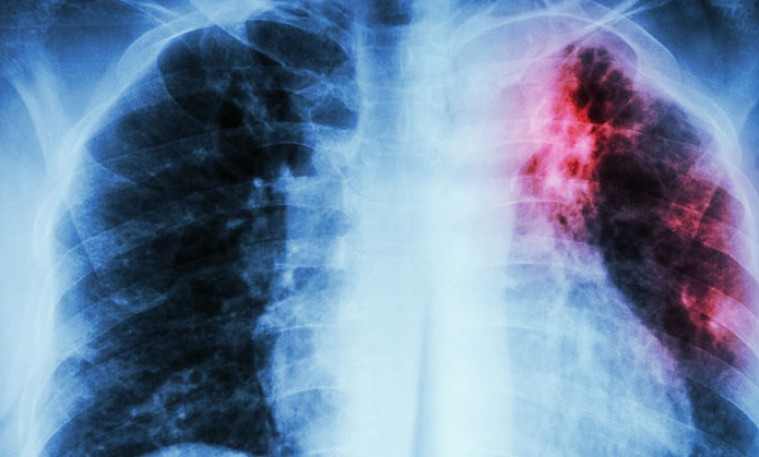

Сүрьеэгээр өвдсөн хүн 15-20 хүнд халдвар тараах эрсдэлтэй байдаг